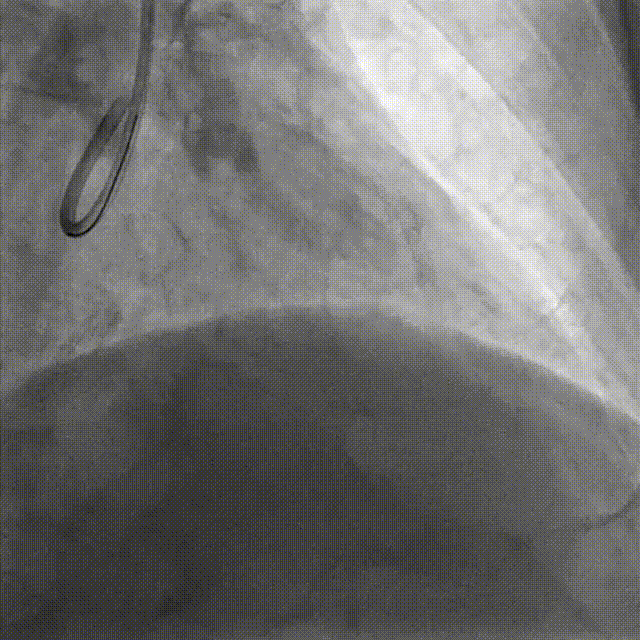

DES Deployment & Optimization DES 4.0*20mm → NC 4.0*12mm @ 20atm

Final Results